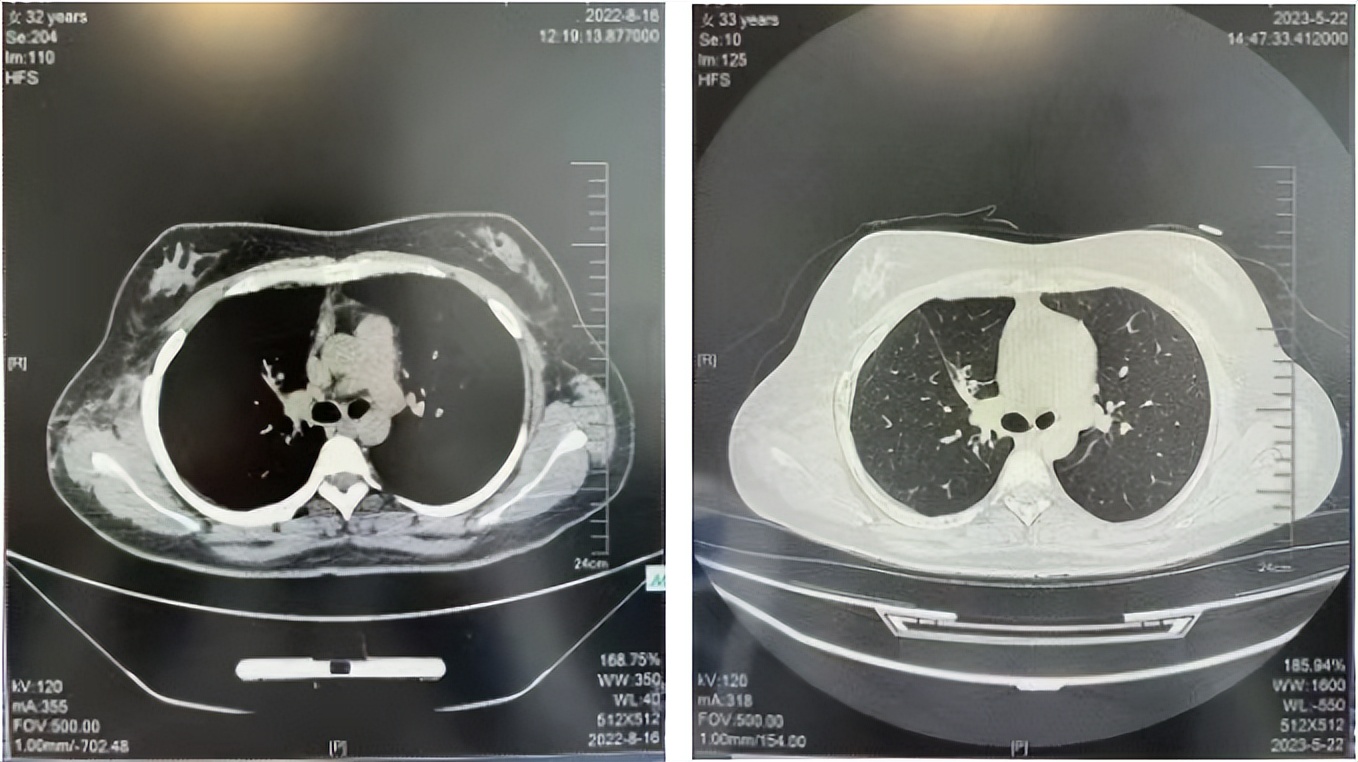

2016年1月复查CT提示支气管截断可见新发小结节,一线治疗采用培美曲塞+DDP方案化疗4周期(培美曲塞3.36,DDP 480mg)。化疗后复查胸部CT:右肺见不规则结节样影,最大层面大小约19mm*8mm,较前比较明显增大,疗效评估PD。2017.3-2017.4予单药多西他赛化疗3周期,疗效评估SD。2018年5月末复查CT提示结节较前增大,评效为PD,2018年6-10月予多西他赛+CBP化疗4周期,疗效评估SD。2022年5月患者出现活动后气短,复查胸部CT示右肺膨胀不良;右侧胸腔积液增多。胸腔积液包埋病理示符合肺腺癌细胞。行NGS基因检测:EML4:exon13-ALK:exon20融合。PD-L1(克隆号22C3)TPS<1%。

临床诊断:右肺上叶恶性肿瘤rT0N0M1a IVA期(第9版分期);恶性胸腔积液。

诊疗经过:2022年5月始口服克唑替尼3个月,出现肝功能异常(DILI 2级伴临床症状),改用恩沙替尼靶向治疗至今,目前评效为维持PR。恩沙替尼应用期间出现轻度肝功能异常(DILI 1级),对症处理后好转。截止目前PFS 33个月。

2022.08

2023.05

56岁,女性,无吸烟史饮酒史,既往体健。2023年02月患者体检发现肺占位性病变,胸部增强CT:右肺下叶后基底段结节;右侧锁骨上及纵隔内多发淋巴结肿大。PET-CT:右肺下叶周围型肺癌可能性大;1R、2L、3P、4R、4L及7组淋巴结转移可能性大。2023年02月就诊于本院胸外科行超声胃镜下纵隔肿物穿刺活检术,病理:结合免疫组化,符合肺腺癌。行NGS基因检测:EML4:exon20-ALK:exon20融合。PD-L1(克隆号22C3)TPS=55%。

临床诊断:右肺下叶恶性肿瘤cT1bN3M0,IIIB(第9版分期),纵隔淋巴结继发恶性肿瘤,锁骨上淋巴肿继发恶性肿瘤

治疗经过:2023年3月27日始行恩沙替尼靶向治疗至今,最佳疗效为PR,末次评效为维持PR。期间出现轻度肝功能异常(DILI 1级),对症处理后好转。截止目前PFS为26个月。

2023年2月20日基线检查

2024年6月复查PR(最佳疗效)

2024年12月复查维持PR

2025年3月复查维持PR